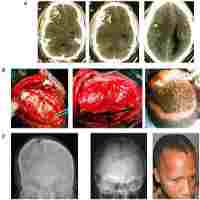

| Abstract | Background: In patients with severe traumatic brain injury (sTBI) treated with decompressive craniectomy (DC), factors affecting the success of later cranioplasty are poorly known. Objective: We sough to investigate if injury- and treatment-related factors, and state of recovery could predict the risk of major complications in cranioplasty requiring implant removal, and how these complications affect the outcome. Methods: A retrospective cohort of 40 patients with DC following sTBI and subsequent cranioplasty was studied. Non-injury related factors were compared with a reference population of 115 patients with DC due to other conditions. Results: Outcome assessed one day before cranioplasty did not predict major complications leading to implant removal. Successful cranioplasty was associated with better outcome, whereas a major complication attenuates patient recovery: in patients with favorable outcome assessed one year after cranioplasty, major complication rate was 7%, while in patients with unfavorable outcome the rate was 42% (p=0.003). Of patients with traumatic subarachnoid hemorrhage (tSAH) on admission imaging 30% developed a major complication, while none of patients without tSAH had a major complication (p=0.014). Other imaging findings, age, admission Glasgow coma scale, extracranial injuries, length of stay at ICU, cranioplasty materials, and timing of cranioplasty were not associated with major complications. Conclusion: A successful cranioplasty after sTBI and DC predicts favorable outcome one year after cranioplasty, while stage of recovery before cranioplasty does not predict cranioplasty success or failure. tSAH on admission imaging is a major risk factor for a major complication leading to implant removal. |